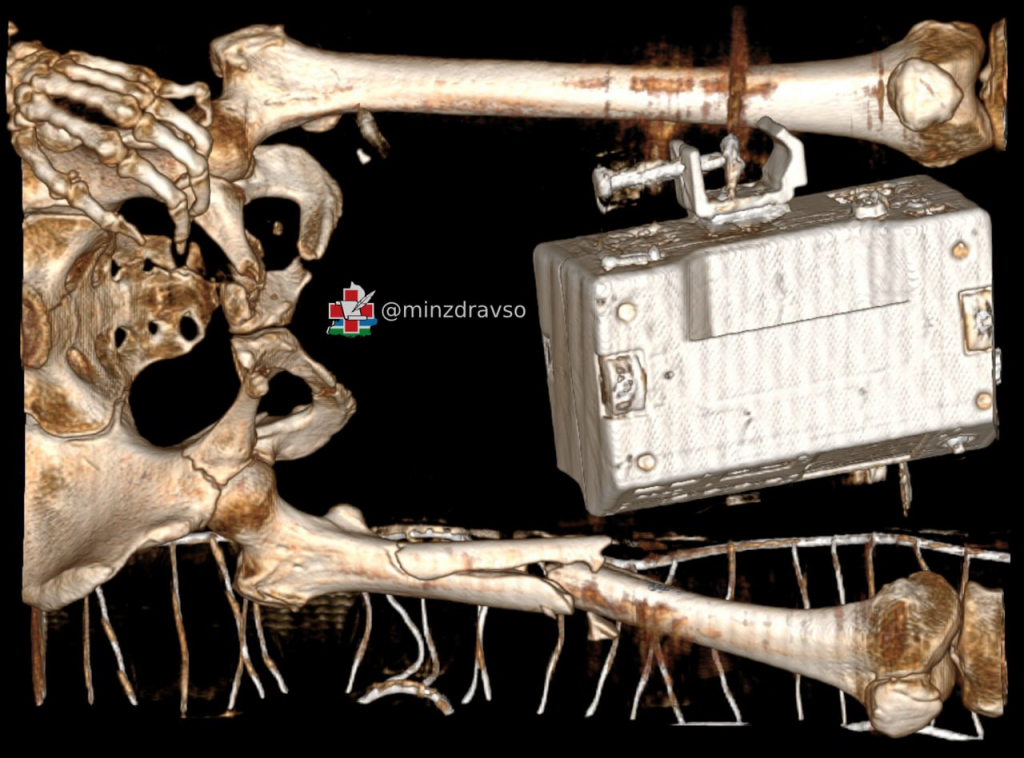

Специалисты нескольких отделений Верхнепышминской центральной городской клинической больницы общими усилиями спасли 50-летнюю женщину, которая выпала из окна четвёртого этажа. У пациентки были тяжёлые травмы таза и бедра, которые сопровождались массивным внутренним кровотечением. Борьба за её возвращение к нормальной жизни длилась более 120 дней, в течение которых врачи провели ей пять сложнейших оперативных вмешательств.

Выпавшая из окна четвёртого этажа 50-летняя свердловчанка получила множественные травмы и в тяжёлом состоянии была доставлена бригадой скорой медицинской помощи в приёмный покой Верхнепышминской центральной городской клинической больницы. По результатам обследования врачи диагностировали у неё нестабильное повреждение таза и многооскольчатый перелом бедра, а также геморрагический шок II степени.

«Такое сочетание повреждений сопровождается массивным внутренним кровотечением с большой кровопотерей, напрямую угрожающей жизни. По жизненным показаниям пациентке была оперативно выполнена фиксация таза и бедра стержневым аппаратом внешней фиксации и проведено переливание крови», — рассказал заведующий травматологическим отделением Верхнепышминской ЦГКБ Андрей Репин.

В течение полутора месяцев пациентка находилась на интенсивной терапии в реанимационно-анестезиологическом отделении, из них 30 дней она была подключена к аппарату искусственной вентиляции лёгких. Верхнепышминские врачи и медсёстры круглосуточно боролись за её жизнь, проводили этапное оперативное лечение и многократные повторные гемотрансфузии — в общей сложности за это время ей перелили около 5 литров компонентов крови. Ситуация усугублялась большой массой тела женщины из-за ожирения II степени, которое негативно сказывалось на состоянии свердловчанки.

«Травма таза традиционно считается одной из самых сложных областей травматологии в связи с высокими рисками для жизни и здоровья пациентов и технической сложностью оперативных методов лечения. Чтобы восстановить форму повреждённых костей и стабилизировать переломы для правильного сращения и восстановления опорно-двигательной функции, потребовались пять сложнейших оперативных вмешательств на тазовом кольце и бедренной кости», — пояснил Андрей Репин.